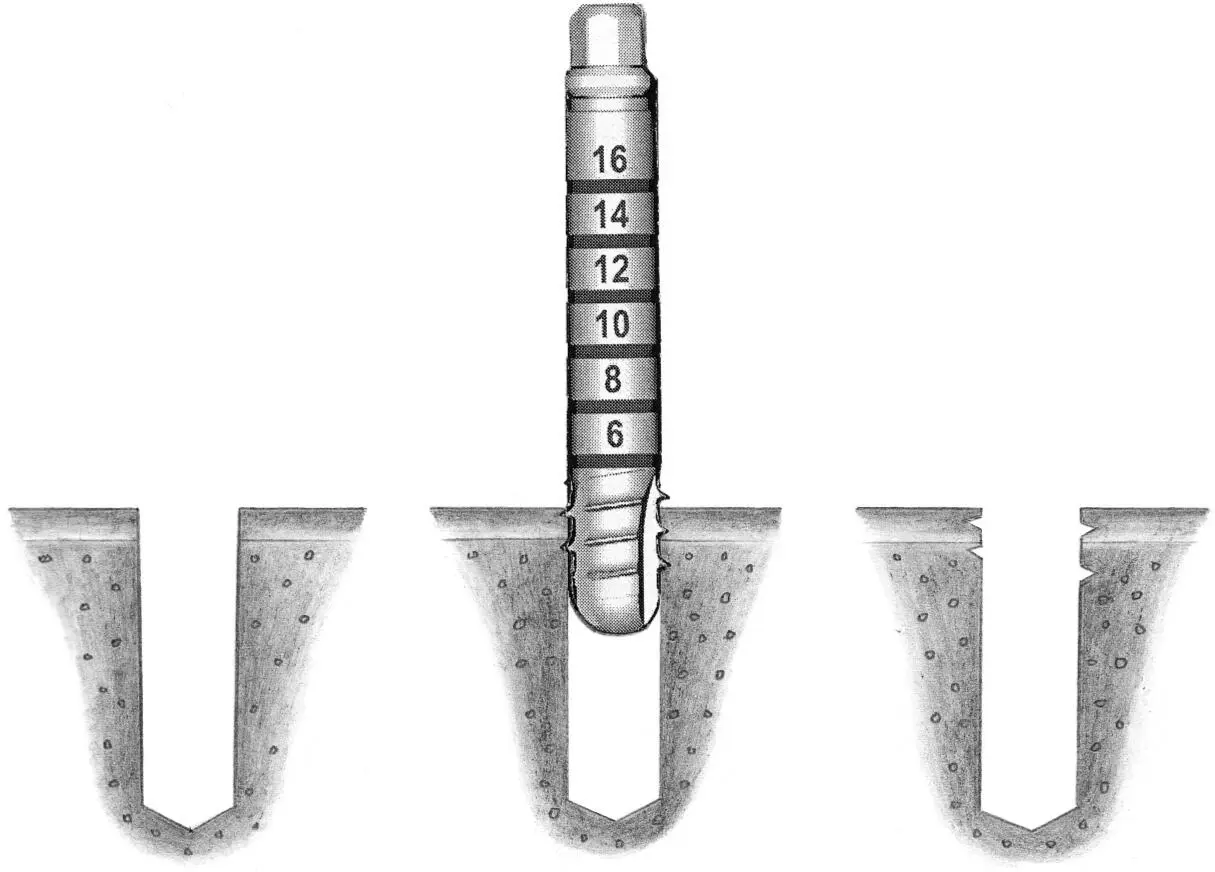

Fig 1-4 Pretapping of implant sites with bone of varying density.

Fig 1-4a Tapping of the bone in the implant site is performed when the bone structure is uniformly dense (ie, type 1 bone). This is done through the entire depth of the implant bed.

Fig 1-4b If the alveolar ridge is partially dense (ie, type 2), tapping of the implant site to one third of the predetermined depth is done within the crestal area.

Fig 1-4c When the alveolar ridge is predominantly cancellous bone (ie, types 3 and 4), no tapping of the bone is required prior to implant placement.